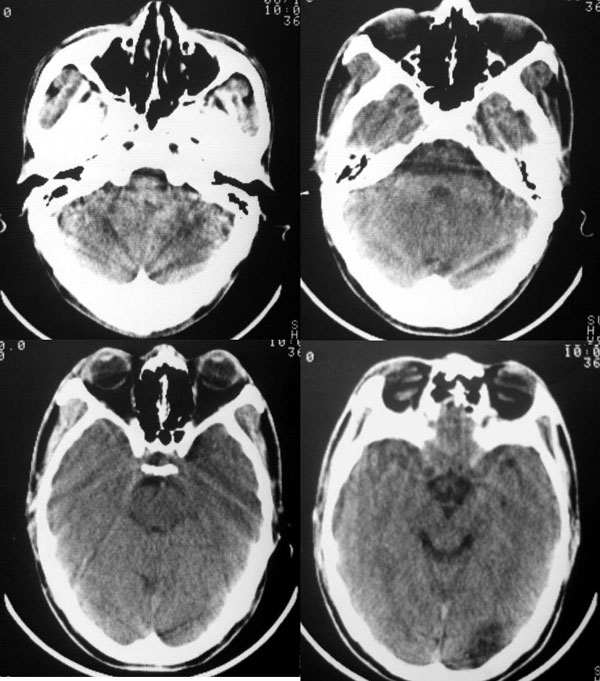

以下是引用dyqct在2006-11-9 15:04:00的发言:[br]左枕叶、双顶叶各见一处似三角形低密度区,边界尚清楚,无占位效应,累及皮质,白质侧未见灰质影。余所见未见异常。[br]考虑:1、脑软化灶;[br] 2、不支持脑裂畸形,该病病变区两侧应有灰质带——即灰质异位,临床上常有顽固性颠痫。当然了脑软化灶也偶会出现颠痫。

以下是引用守望可可西里在2006-11-9 15:06:00的发言:[br][br] 1.左侧枕叶低密度与侧脑室相通,考虑开唇型脑裂畸形。[br] 2.双侧顶叶低密度考虑局部脑沟异常扩大,发育问题。